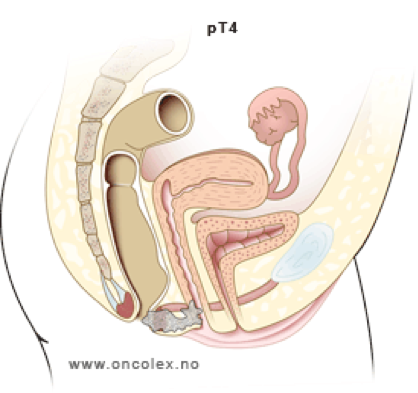

T4 |

Tumör oavsett storlek som engagerar angränsande organ |

- Med T4 avses inväxt i andra organ, exempelvis vagina, uretra, urinblåsa eller prostata. Inväxt i sfinktermuskulatur klassas inte som T4. När det gäller inväxt i annan sfinkternära muskulatur, såsom m. levator ani eller m. puborectalis, saknas tydlig vägledning i litteraturen, men vårdprogramsgruppen anser att en sådan tumör inte bör klassas som T4.

Figur 5. Schematisk bild av T-stadium vid analcancer